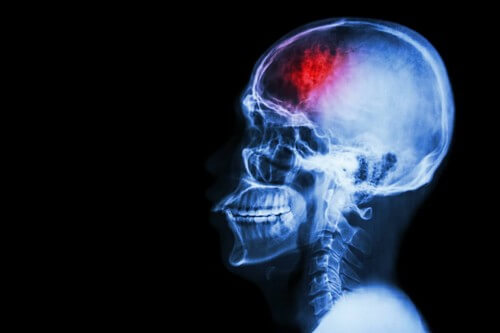

Un ictus è un’improvvisa anomalia del flusso sanguigno nel cervello che provoca sintomi fisici e mentali che potrebbero protrarsi nel tempo.

Colpisce circa 130.000 persone l’anno, di cui oltre 300.000 manifesteranno limitazioni funzionali. Si tratta, dunque, di una condizione con elevata incidenza, in aumento. Nonostante ciò, è bene sapere che il 90% degli ictus può essere prevenuto.

In Italia è la terza causa di morte della popolazione, nonché la prima causa di morte tra le donne. Si tratta anche della prima causa di invalidità nell’adulto; il 35% dei casi avviene in età lavorativa, il che significa che non si tratta di un problema che interessa solo gli anziani.